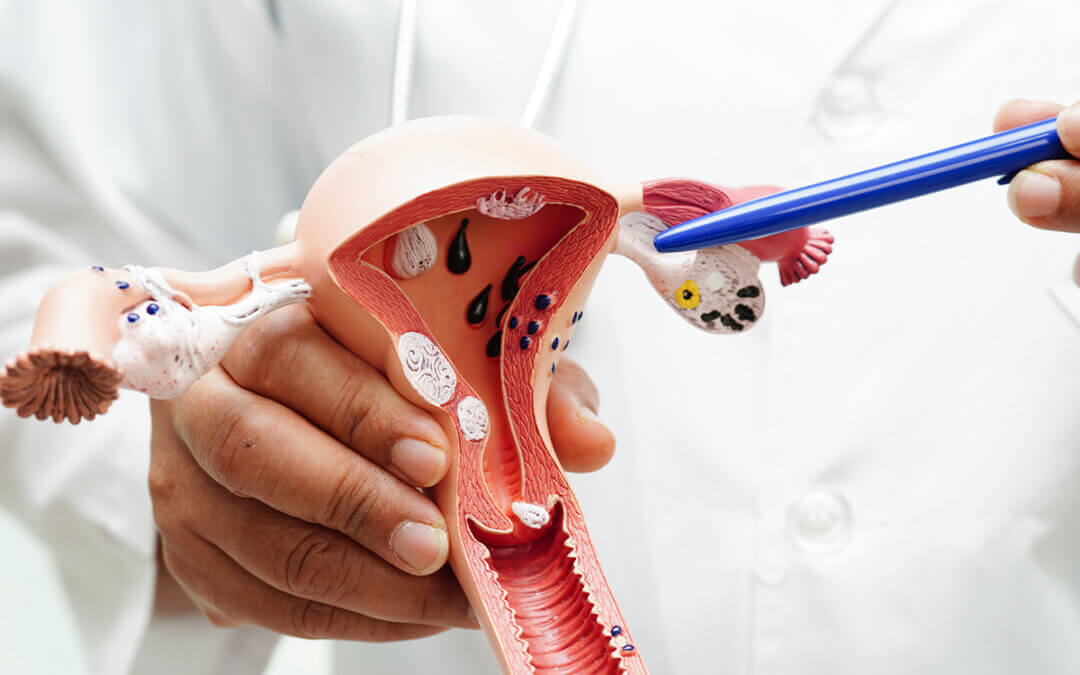

Cervical cancer originates in the cells of the cervix, which is the lower, narrow portion of the uterus that connects to the vagina. Most cervical cancers begin in the transformation zone — the area where the cervix transitions between two types of cells: squamous cells (flat cells lining the ectocervix) and glandular cells (column-shaped cells lining the endocervix).

The two main types of cervical cancer are squamous cell carcinoma, accounting for about 70–90% of all cases, and adenocarcinoma, which develops from the glandular cells. In rare cases, both types may be present simultaneously. Cervical cancer is usually slow-growing, taking years to develop from precancerous lesions into full-blown cancer — which is exactly why early screening is so powerful.

Diagnosis and Treatment

When a Pap smear or HPV test returns an abnormal result, the next step is usually a colposcopy — a procedure in which the doctor examines the cervix under magnification and may take a small tissue sample (biopsy) for laboratory analysis. If precancerous changes are confirmed, treatment options such as LEEP (loop electrosurgical excision procedure), cryotherapy, or cone biopsy can remove the abnormal tissue before it becomes invasive cancer.

For diagnosed cervical cancer, treatment depends on the stage and may include surgery, radiation therapy, chemotherapy, or a combination. Early-stage cervical cancer (Stage I and II) has survival rates above 80–90% with appropriate treatment. Advanced-stage cancer is significantly harder to treat, which is why early detection is so critically important.